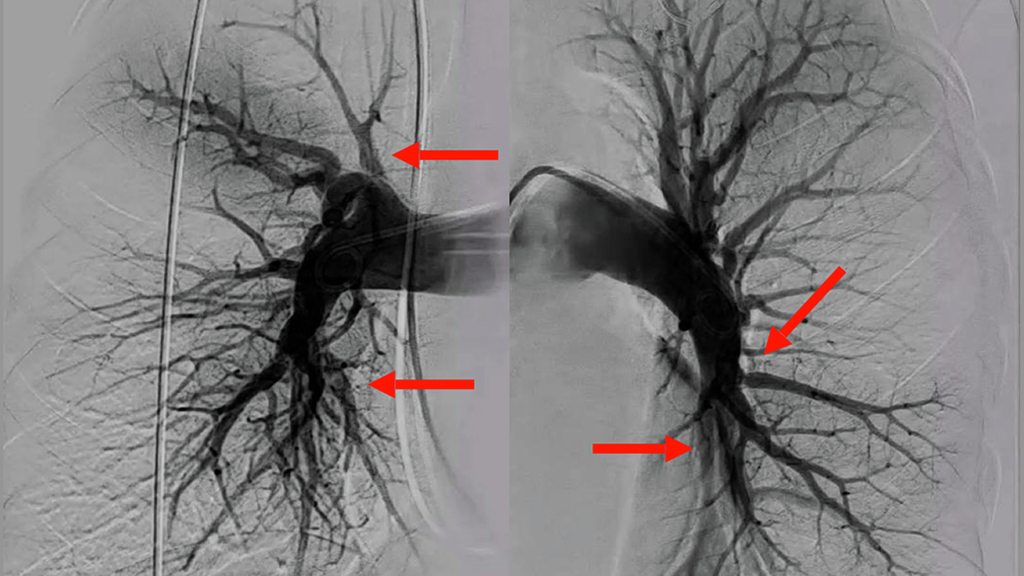

A pulmonary angiogram shows areas of blood clot (arrows) in the lungs

Figure 1: Pulmonary angiogram of the lungs demonstrating areas of chronic thrombus (arrows) leading to vessel narrowing and reduced blood flow.

A CT scan in the ER revealed extensive large bilateral pulmonary emboli (Figure 1) with RV strain and right ventricular dysfunction on echocardiogram, and severely elevated pulmonary artery pressures concerning for acute-on-chronic PE.

A repeat right heart catheterization and diagnostic digital subtraction pulmonary angiography were performed, and found severe pulmonary hypertension, large bilateral perfusion defects and findings typical of proximal chronic thromboembolic disease.